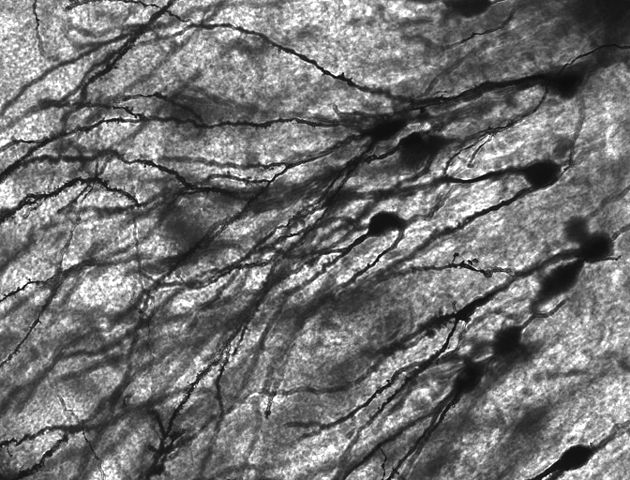

| DescriptionGyrus Dentatus 40x.jpg |

Image of Golgi stained neurons in the dentate gyrus of an epilepsy patient. 40 times magnification.